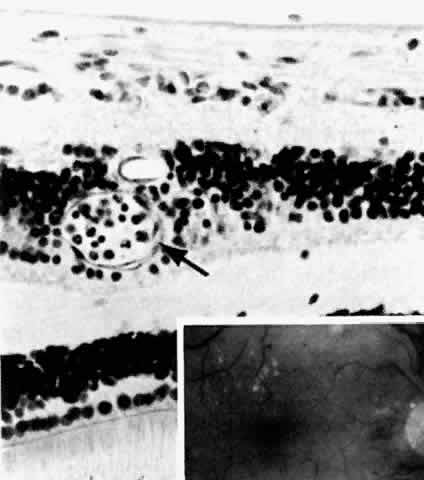

The earliest manifestation of diabetic retinopathy is the appearance of microaneurysms (Fig. 5, Color Fig. D). They appear as small red dots clinically and often are seen more readily on fluorescein angiography, where they fill and leak, with staining of the vessel wall.35 Histologically they are small “outpouchings” of the capillary vessel wall and are usually saccular but occasionally fusiform in shape. They can occur anywhere along the capillary network between the arteriole and venule.18 Some microaneurysms, however, do not fill with fluorescein and have been shown to be thin-walled capillary outpouchings filled with erythrocytes. They may represent either one stage of microaneurysm formation or a specific type of it.36

Fig. 5. Retinal capillary microaneurysm (arrow) is characterized by its thin wall and location in the capillary area of the retina (middle retinal layers) rather than the major vessel area (inner retinal layers). Inset. Fundus appearance of microaneurysms and hard or waxy exudates. (Main figure, H&E, × 176)